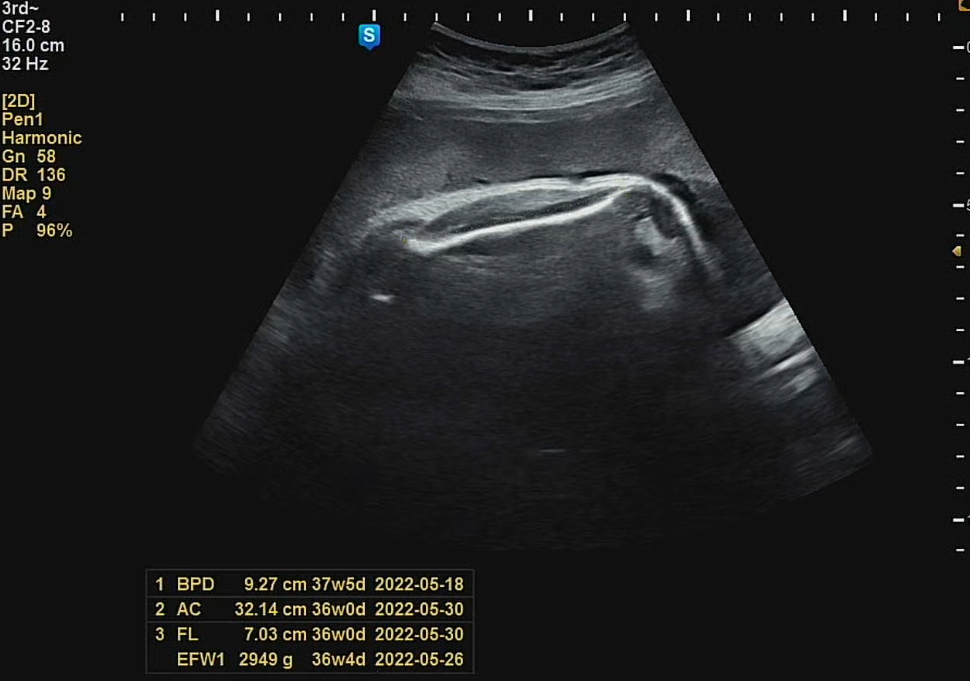

이번에도 역시 머리둘레는 주수에 맞는 크기였고, 배둘레, 다리 길이는 살짝 짧은 편이었다. 그래도, 세상 밖에 나와서 건강하게만 쑥쑥 자라준다면야!! 가장 걱정했던 체중은 일주일 전 검사 때 2,675g 에서 2,949g로 쪘다. 체중이 늘어나는 추이를 봤을 때 다음주 출산 때는 3kg를 충분히 넘길 수 있을 것 같았다.

현재 주수때는 하루에 20~30g씩 체중이 찐다고 했는데, 우리 까꿍이는 40g 가까이 꾸준히 체중이 붙고 있었다. 휴, 걱정한 만큼 아내가 세끼 꼬박꼬박 챙겨 먹고 해서 까꿍이가 엄마 영양분 잘 받아서 컸나 보다😋